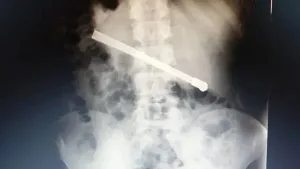

Insólito: un preso en Rosario se tragó una bombilla y tuvieron que operarlo de urgencia agosto 12, 2025